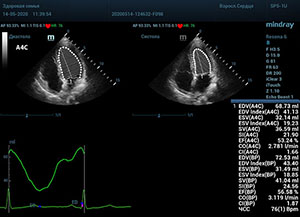

С появлением В режима реализовалась возможность визуализации всех сегментов миокарда из парастернальных и апикальных сечений. Метод Teicholtz в широкой практике сменился методом дисков. Метод дисков, или метод Simpson, позволяет разбить левый желудочек на 20 дисков, с расчетом объема каждого из них. Используя 2 перпендикулярных сечения, апикальные двух и четырех камерное, мы приближаемся к значению реального объема левого желудочка. Исследователь обводит интерфейс эндокард – кровь в фазу диастолы и фазу систолы. Линия простирается от кольца митрального клапана и до кольца митрального клапана, четко разграничивая объем желудочка от предсердия. Для достоверного изменения необходимо использовать ЭКГ канал.

Что могут предложить современные приборы? Приборы нашего времени являются мощными вычислительными машинами, способными обрабатывать полученную информацию даже без помощи человека. Система автоматического вычисления фракции выброса – AUTO EF на приборах серии Resona компании Mindray сделает все за вас. За пару секунд прибор сам отыщет нужную фазу сердечного цикла и произведёт измерение и расчеты, а также покажет график изменения объема в сердечном цикле. От Вас требуется только получить качественное 4С и 2С сечение. Впрочем, прибор всегда оставляет возможность коррекции, если доктор имеет свое мнение на расположение точек планиметрии или момента измерения по ЭКГ каналу.